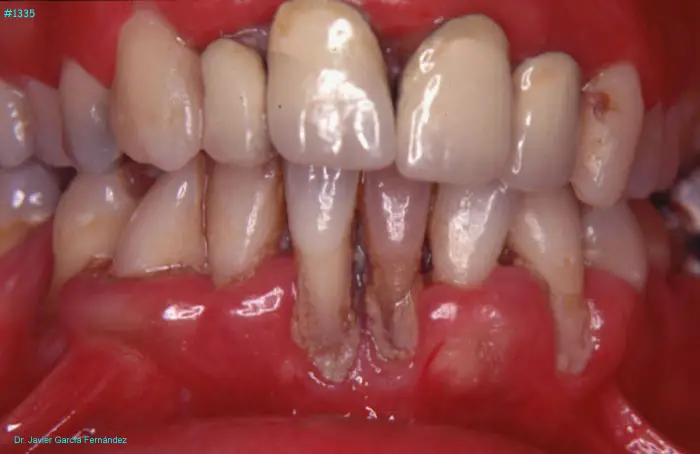

Atlas of Surgical Techniques in Periodontics. Chapter III. Atlas de Técnicas Quirúrgicas en Periodoncia